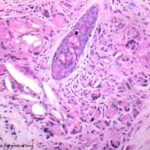

Histopathology. A nonallergic foreign-body reaction typically shows a granulomatous response marked by histiocytes and giant cells surrounding foreign material. Often, some of the giant cells are of the foreign-body type, in which the nuclei are in haphazard array. In addition, lymphocytes are usually present, as may be plasma cells and neutrophils. Frequently, some of the foreign material is seen within macro phages and giant cells, a finding that of course is of great diagnostic value. The most common cause of a foreign-body granuloma is rupture of a hair follicle or follicular cyst, and sometimes only the cyst contents, rather than residual cyst wall, is identifiable . Exogenous substances producing nonallergic foreign-body reactions include silk and nylon sutures , wood or other plant material , paraffin and other oily substances, silicone gel, talc, surgical glove starch powder, and cactus spines. Some of these substances-nylon sutures, wood, talc, surgical glove starch powder, and sea urchin spines-are doubly refractile on polarizing examination. Double refraction often is very helpful in localizing foreign substances. Knife marks in the section may be an additional clue to the presence of particulate foreign matter |